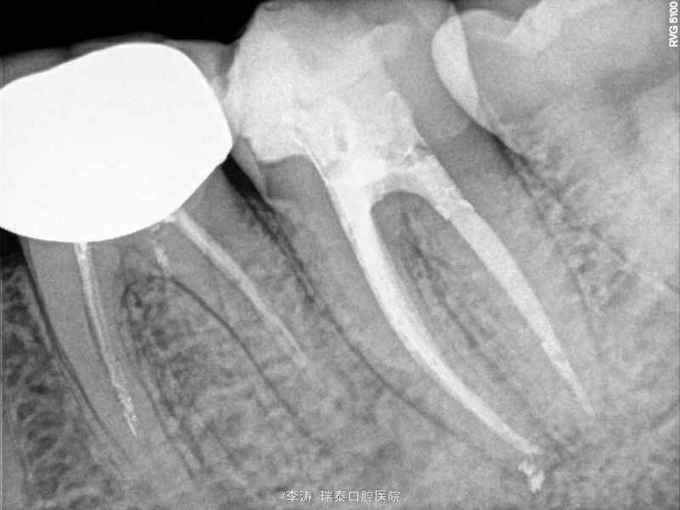

37牙近中深龋,冷-,叩-,x线片近髓

37牙去龋未净时穿髓 行根管治疗,开髓,根管预备,但根管预备封药后两天开始疼痛,叩痛明显,去除封药,未见明显分泌物,根管荡洗干燥后重新封药,但症状一直持续,自服止疼药后缓解,两周以后疼痛消失予以根充